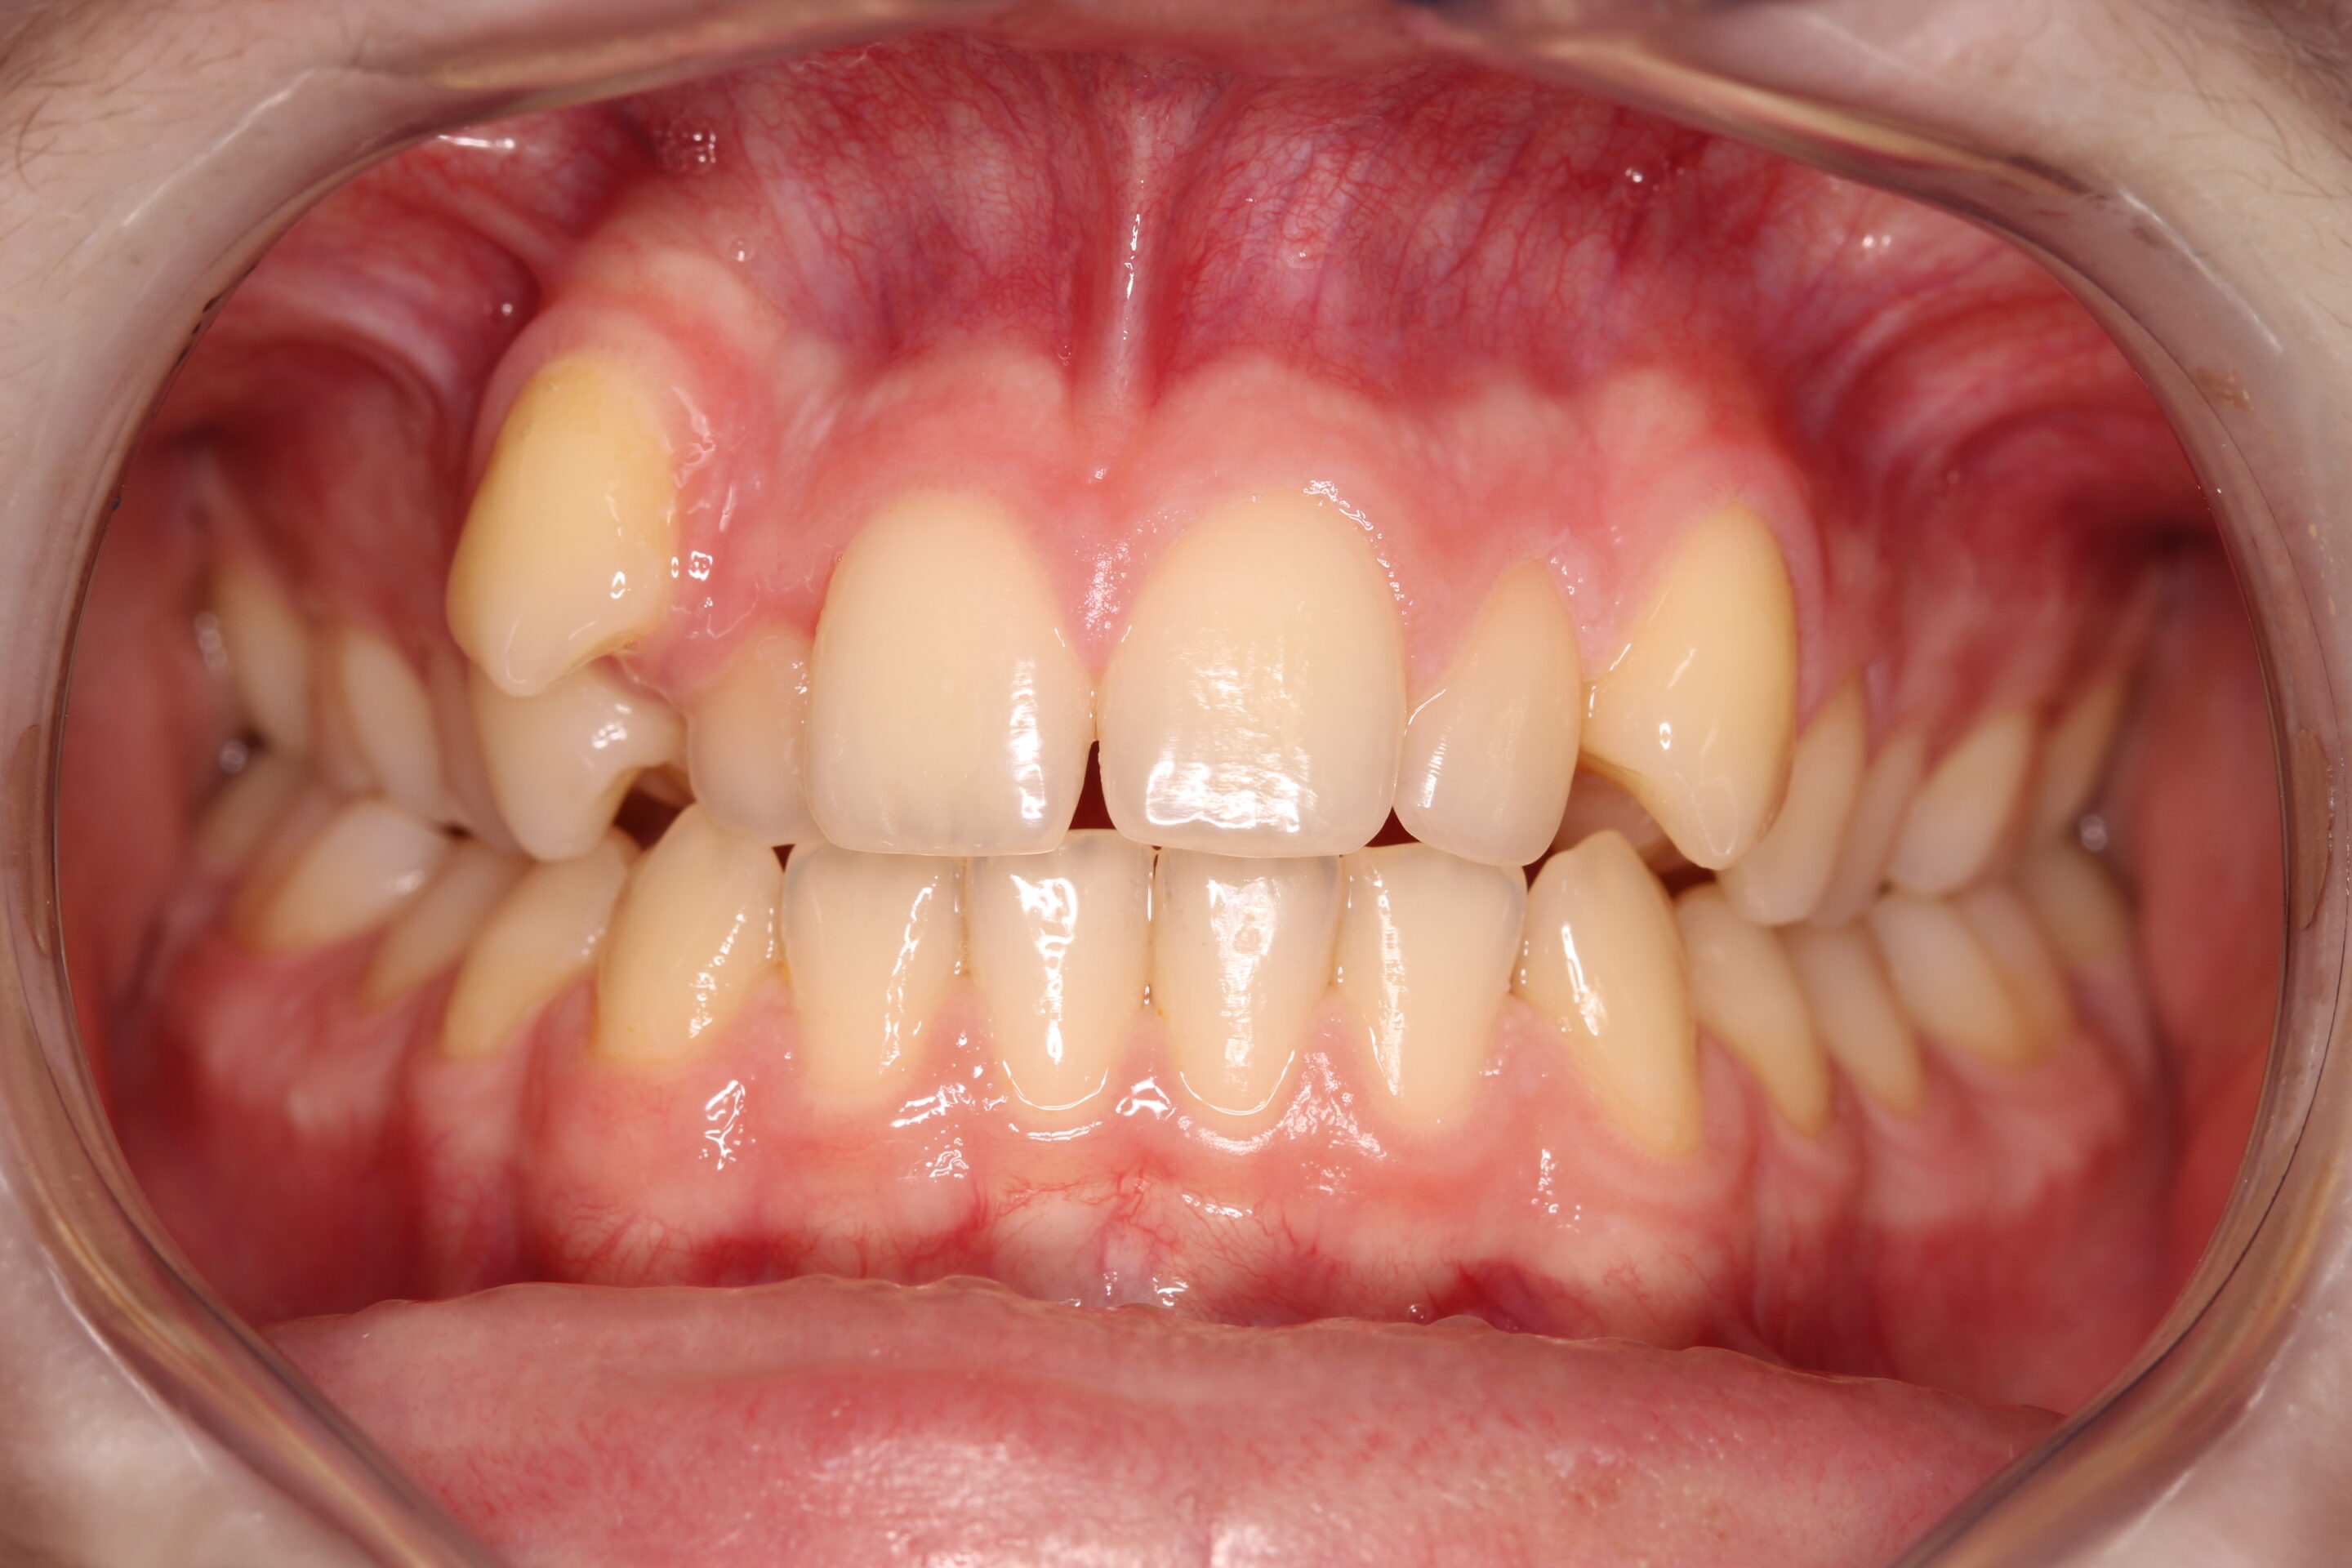

Fogív rendezés

A frontfogak torlódását és a harapás eltérését sikeresen korrigáltuk, így a fogív szabályossá vált, a rágófunkció javult és az esztétikai megjelenés is sokkal harmonikusabb lett.

Fogiv-rendezes-elott

Fogiv-rendezes-utan

Előtte

Utána